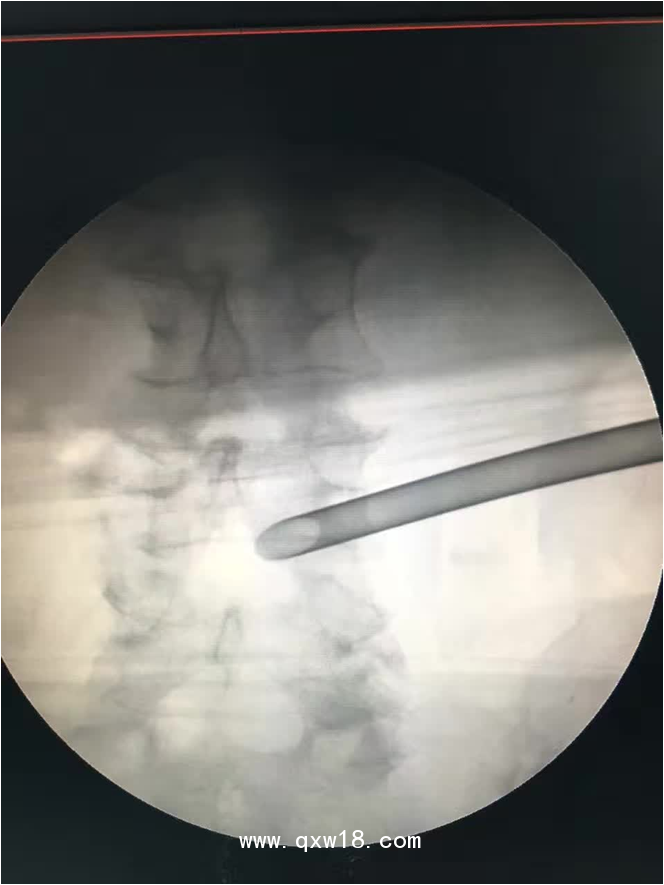

椎間孔鏡品牌椎間孔鏡椎間孔鏡技術(shù)椎間孔鏡培訓(xùn)產(chǎn)品說明:

portant; word-wrap: break-word !important;">椎間孔鏡手術(shù)圍手術(shù)期注意事項:

portant; word-wrap: break-word !important;">一、 術(shù)前常規(guī)注意事項:1?排便應(yīng)通暢,腸腔脹氣,便秘等,嚴(yán)重影響到術(shù)中操作必須的C臂透視的效果。用力排便等將在術(shù)后由于腹壓的增高,而容易導(dǎo)致髓核從修復(fù)的纖維環(huán)破口內(nèi)突出,導(dǎo)致手術(shù)失敗。2?術(shù)前停止服用活血等藥物。如丹參、紅參等。服用阿司匹林的患者需要停藥5天后方才安排手術(shù)。3?由于腰椎局麻手術(shù),不需要全麻,故術(shù)前不需禁食,但術(shù)前一餐也不能飽食,部分患者術(shù)中需靜脈用藥輔助,可能因此引起惡心、嘔吐等反應(yīng)。4?術(shù)前患者應(yīng)配備合適的腰圍并帶進(jìn)手術(shù)室,術(shù)后即刻就需帶上。腰圍寧緊勿松,寧硬勿軟。